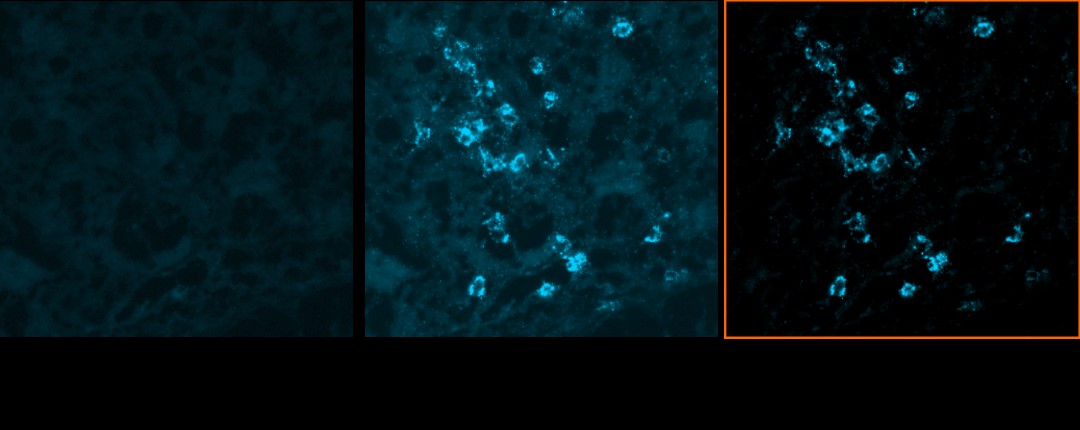

Chipcytometry 还具有 8 logs 的信号动态范围,和传统只具有 2.5 logs 信号范围的技术相比,Chipcytometry 的图片不会出现过饱和的问题,所以即使是微小差异的变化也很容易被发现,对于临床病理的研究具有非常重要的意义。

此外,独特的 Net fluorescence 技术可以去除组织本身带来的自体荧光的影响,即降低背景噪音干扰,因此 Chipcytometry 的影像品质与定量数据非常稳定可靠。